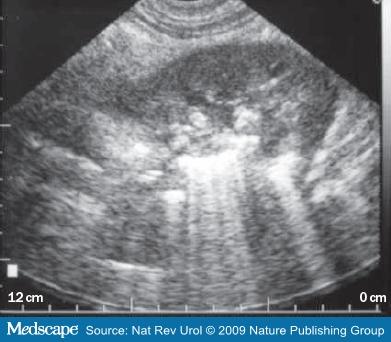

Chronic Pancreatitis

Ongoing inflammation that results in permanent damage

N & V

flatulence

weight loss

Chronic Pancreatitis

Ongoing inflammation that results in permanent damage